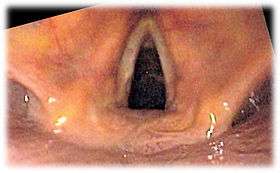

![]() View of the glottis as seen during laryngoscopy | |

Laryngoscopy is endoscopy of the larynx, a part of the throat. It is a medical procedure that is used to obtain a view, for example, of the vocal folds and the glottis. Laryngoscopy may be performed to facilitate tracheal intubation during general anaesthesia or cardiopulmonary resuscitation or for surgical procedures on the larynx or other parts of the upper tracheobronchial tree.